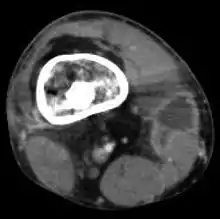

![]() | |

| Osteomyelitis of the 1st toe | |